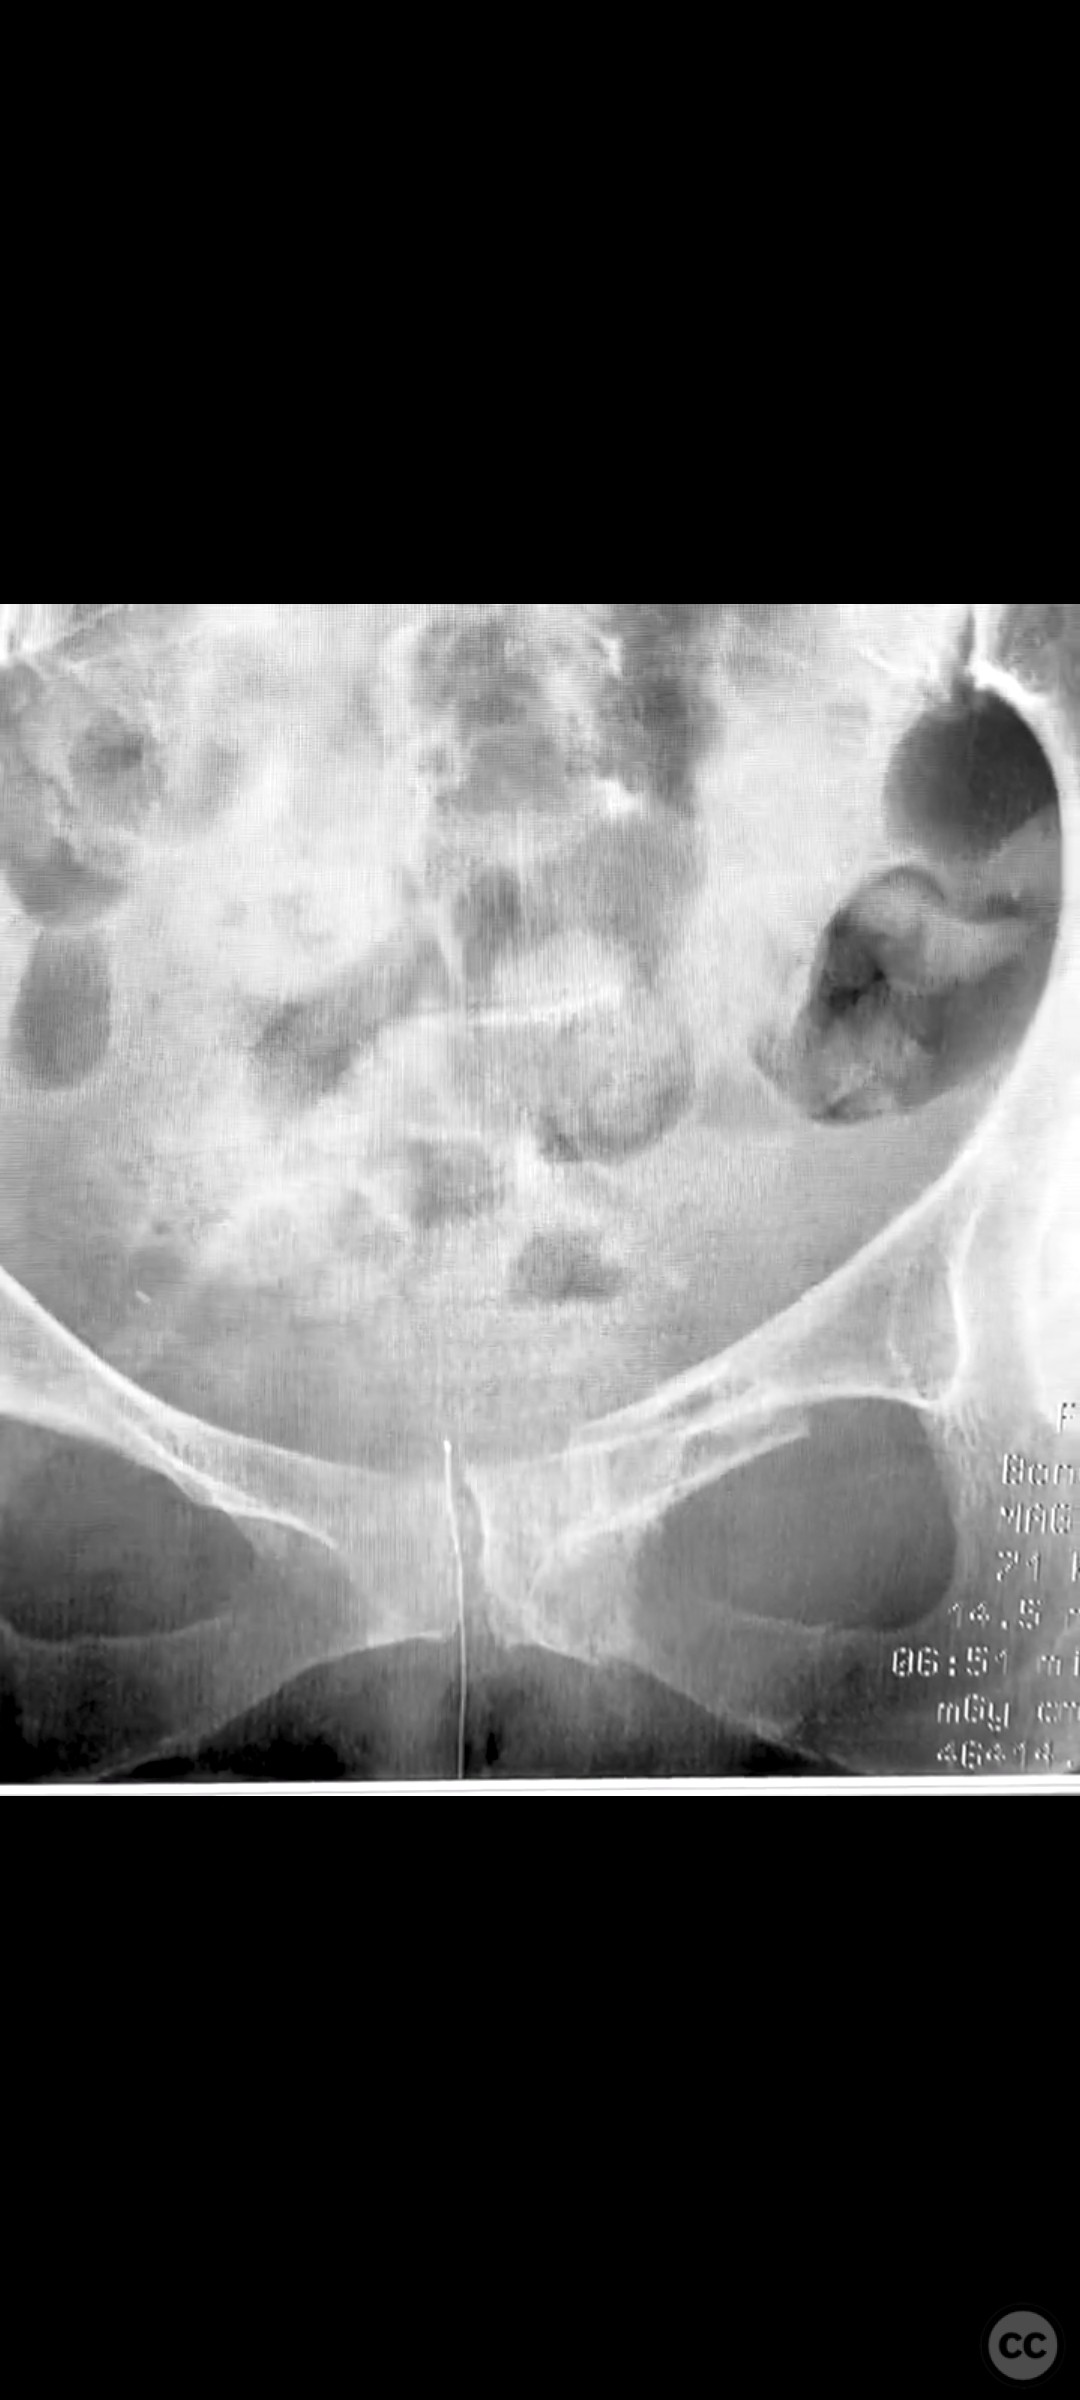

Clinical and radiological findings:  A 74-year-old female presented following a fall from standing height, unable to mobilize due to severe pelvic pain (9/10). Examination under anesthesia with fluoroscopic assessment (AP and inlet views) demonstrated instability and displacement of the pelvic ring with minimal manual compression at the iliac crests. Imaging revealed left-sided posterior iliac/sacral and pubic ramus fractures consistent with an AO/OTA 61-B2 (lateral compression type) pelvic ring injury. No neurovascular deficits were noted.

Planning remarks:  The preoperative plan involved closed reduction of the pelvic ring under fluoroscopic guidance, followed by percutaneous screw fixation of the left posterior iliac/sacral region and the ipsilateral pubic ramus. Detailed preoperative CT imaging was used to plan safe osseous corridors for screw placement, correlating with intraoperative fluoroscopic landmarks.